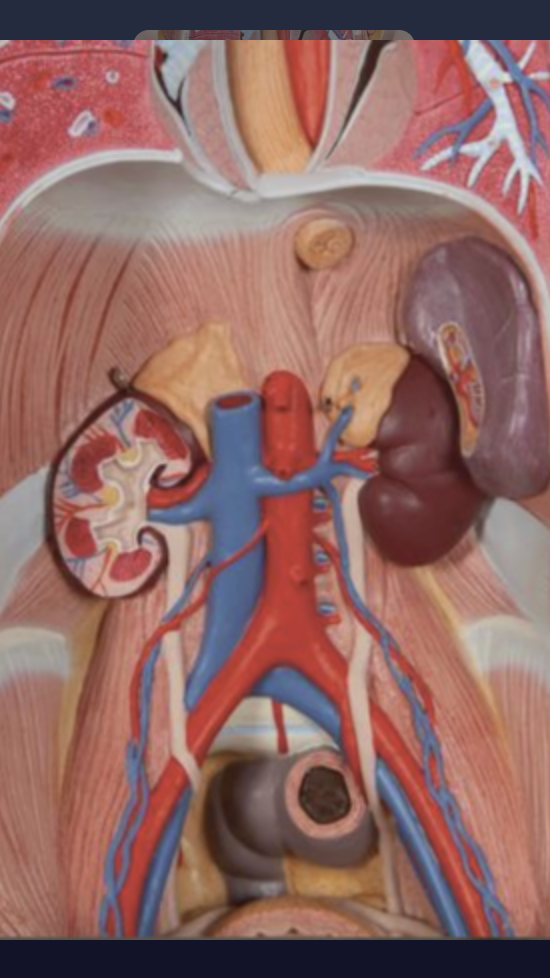

Paired glands on top of the kidneys

Adrenal glands

What is the connective tissue that wraps each adrenal gland?

Capsule

What holds the adrenal glands in place on the kidney’s?

Adipose tissue

Another name for adrenal glands

Suprarenal glands

In this picture, what gland is present?